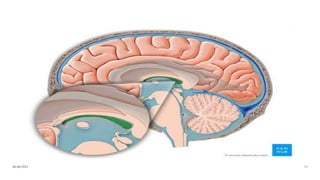

Anatomy of ventricles

About choroid plexus

◦Choroid plexus is present in each ventricles

◦In the lateral ventricles it is only present in the inferior horn

◦Choroid plexus is also located in the interventricular foramina,

the channels between the lateral and the third ventricles. The

choroid plexus in the fourth ventricle is beneath the

cerebellum.